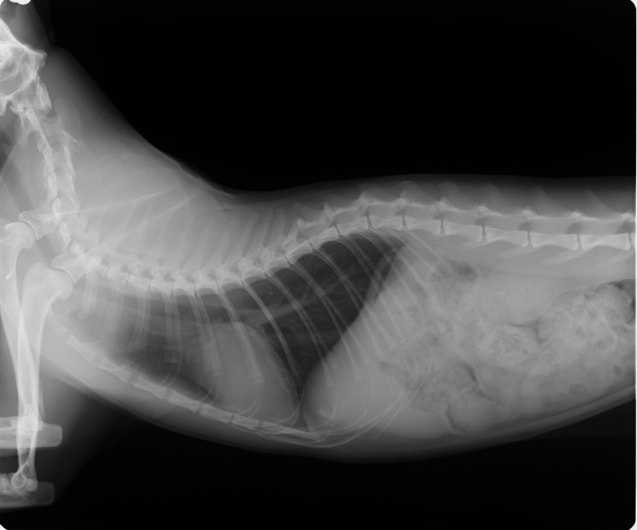

B:胸部レントゲン写真 側面像

胸部レントゲン検査において重度の心拡大と肺水腫が認められた。超音波検査では、重度の僧帽弁閉鎖不全症、三尖弁閉鎖不全症、中程度の大動脈弁閉鎖不全症を合併していることが判明した。三尖弁逆流速度から肺高血圧症が示唆された。